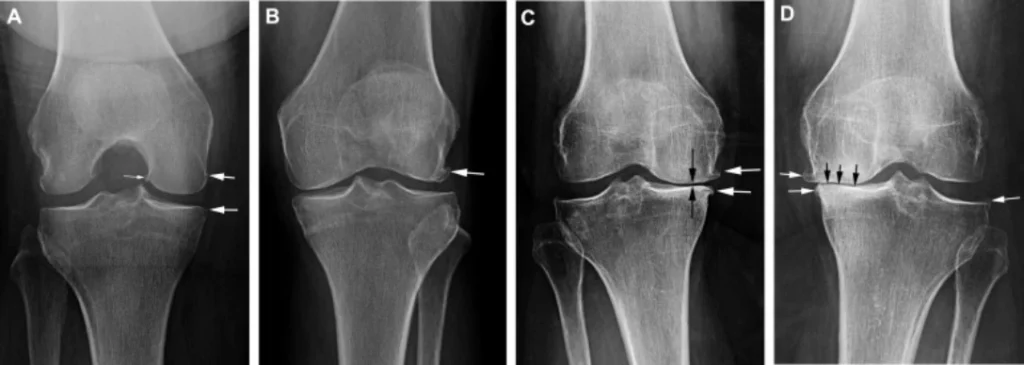

What causes knee osteoarthritis?The ultimate cause of knee pain and other osteoarthritis symptoms is often bone-on-bone friction as the cartilage begins to erode (See Figure 2). Over time, cartilage may wear away completely, leaving the joint vulnerable to permanent damage.

Figure 2. Phases of Osteoarthritic Knee Degeneration (knee osteoarthritis pictures).

(A) Black arrows point to the joint space between the femur and tibia in a healthy knee.

(B) Osteophyte formation is denoted by the white arrow marking the beginning of clinically graded osteoarthritis.

(C) Joint space gradually lessens with disease progression ultimately leading to D) a near complete loss of joint space in severe osteoarthritis, denoted by black arrows.